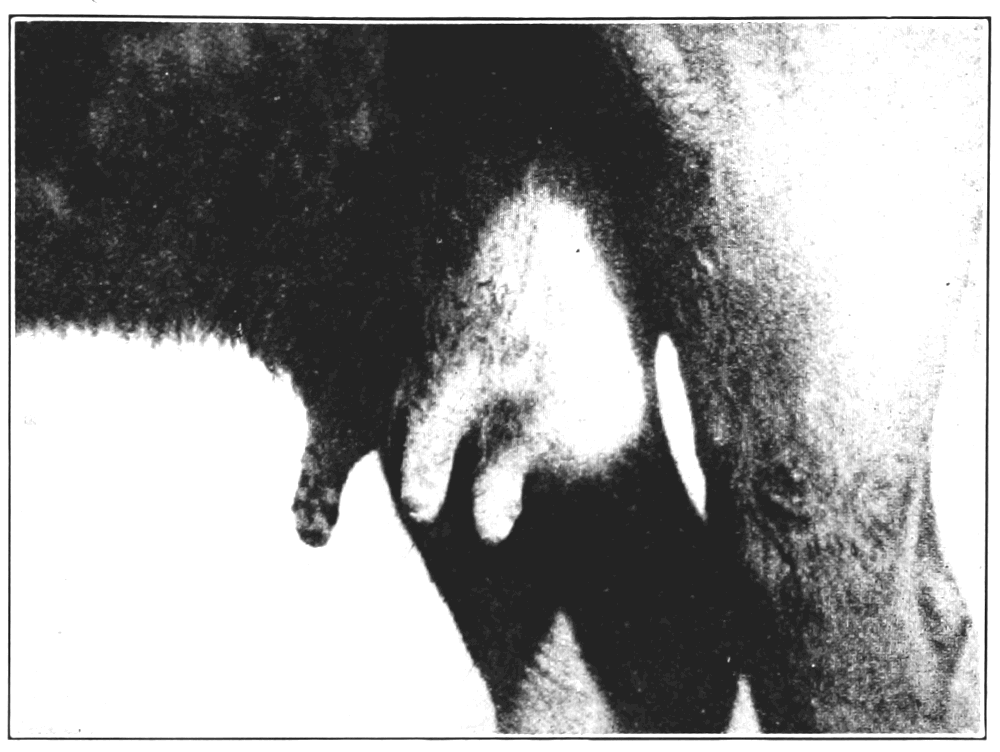

6. A severe form of vaccination in a little child, where the inflammation and eruption spreads from the sore over part of the body and endangers life by blood poisoning or general septicemia 88

As further convincing evidence on this head, I have a Brooklyn death certificate showing the death of a woman hospital nurse six months after vaccination, from multiple abscesses which broke out all over the body in successive crops and continued[Pg 10] for six months notwithstanding the most skillful medical efforts for cure, and finally resulted in death from general vaccinal septicemia. See Figs. 11, 12 and 13, which show other cases of this kind.